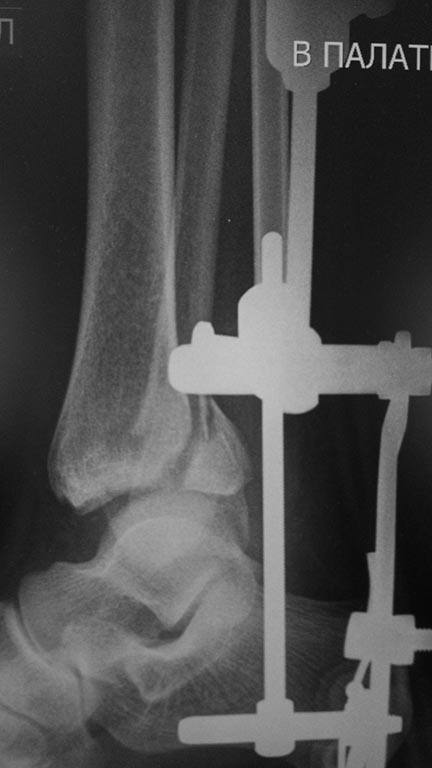

Мужчина, 1987 г.р. получил травму 10.2014. ДТП. Закрытый двухлодыжечный

перелом костей костей левой голени, перелом заднего края большеберцовой

кости с подвывихом стопы кзади, кнаружи. Наложен дистрактор.

Операция 10.2014: закрытая репозиция, остеосинтез спицами,

винтами. В дальнейшем произошло ожидаемое усугубление нарушений

взаимоотношений в голеностопном суставе.